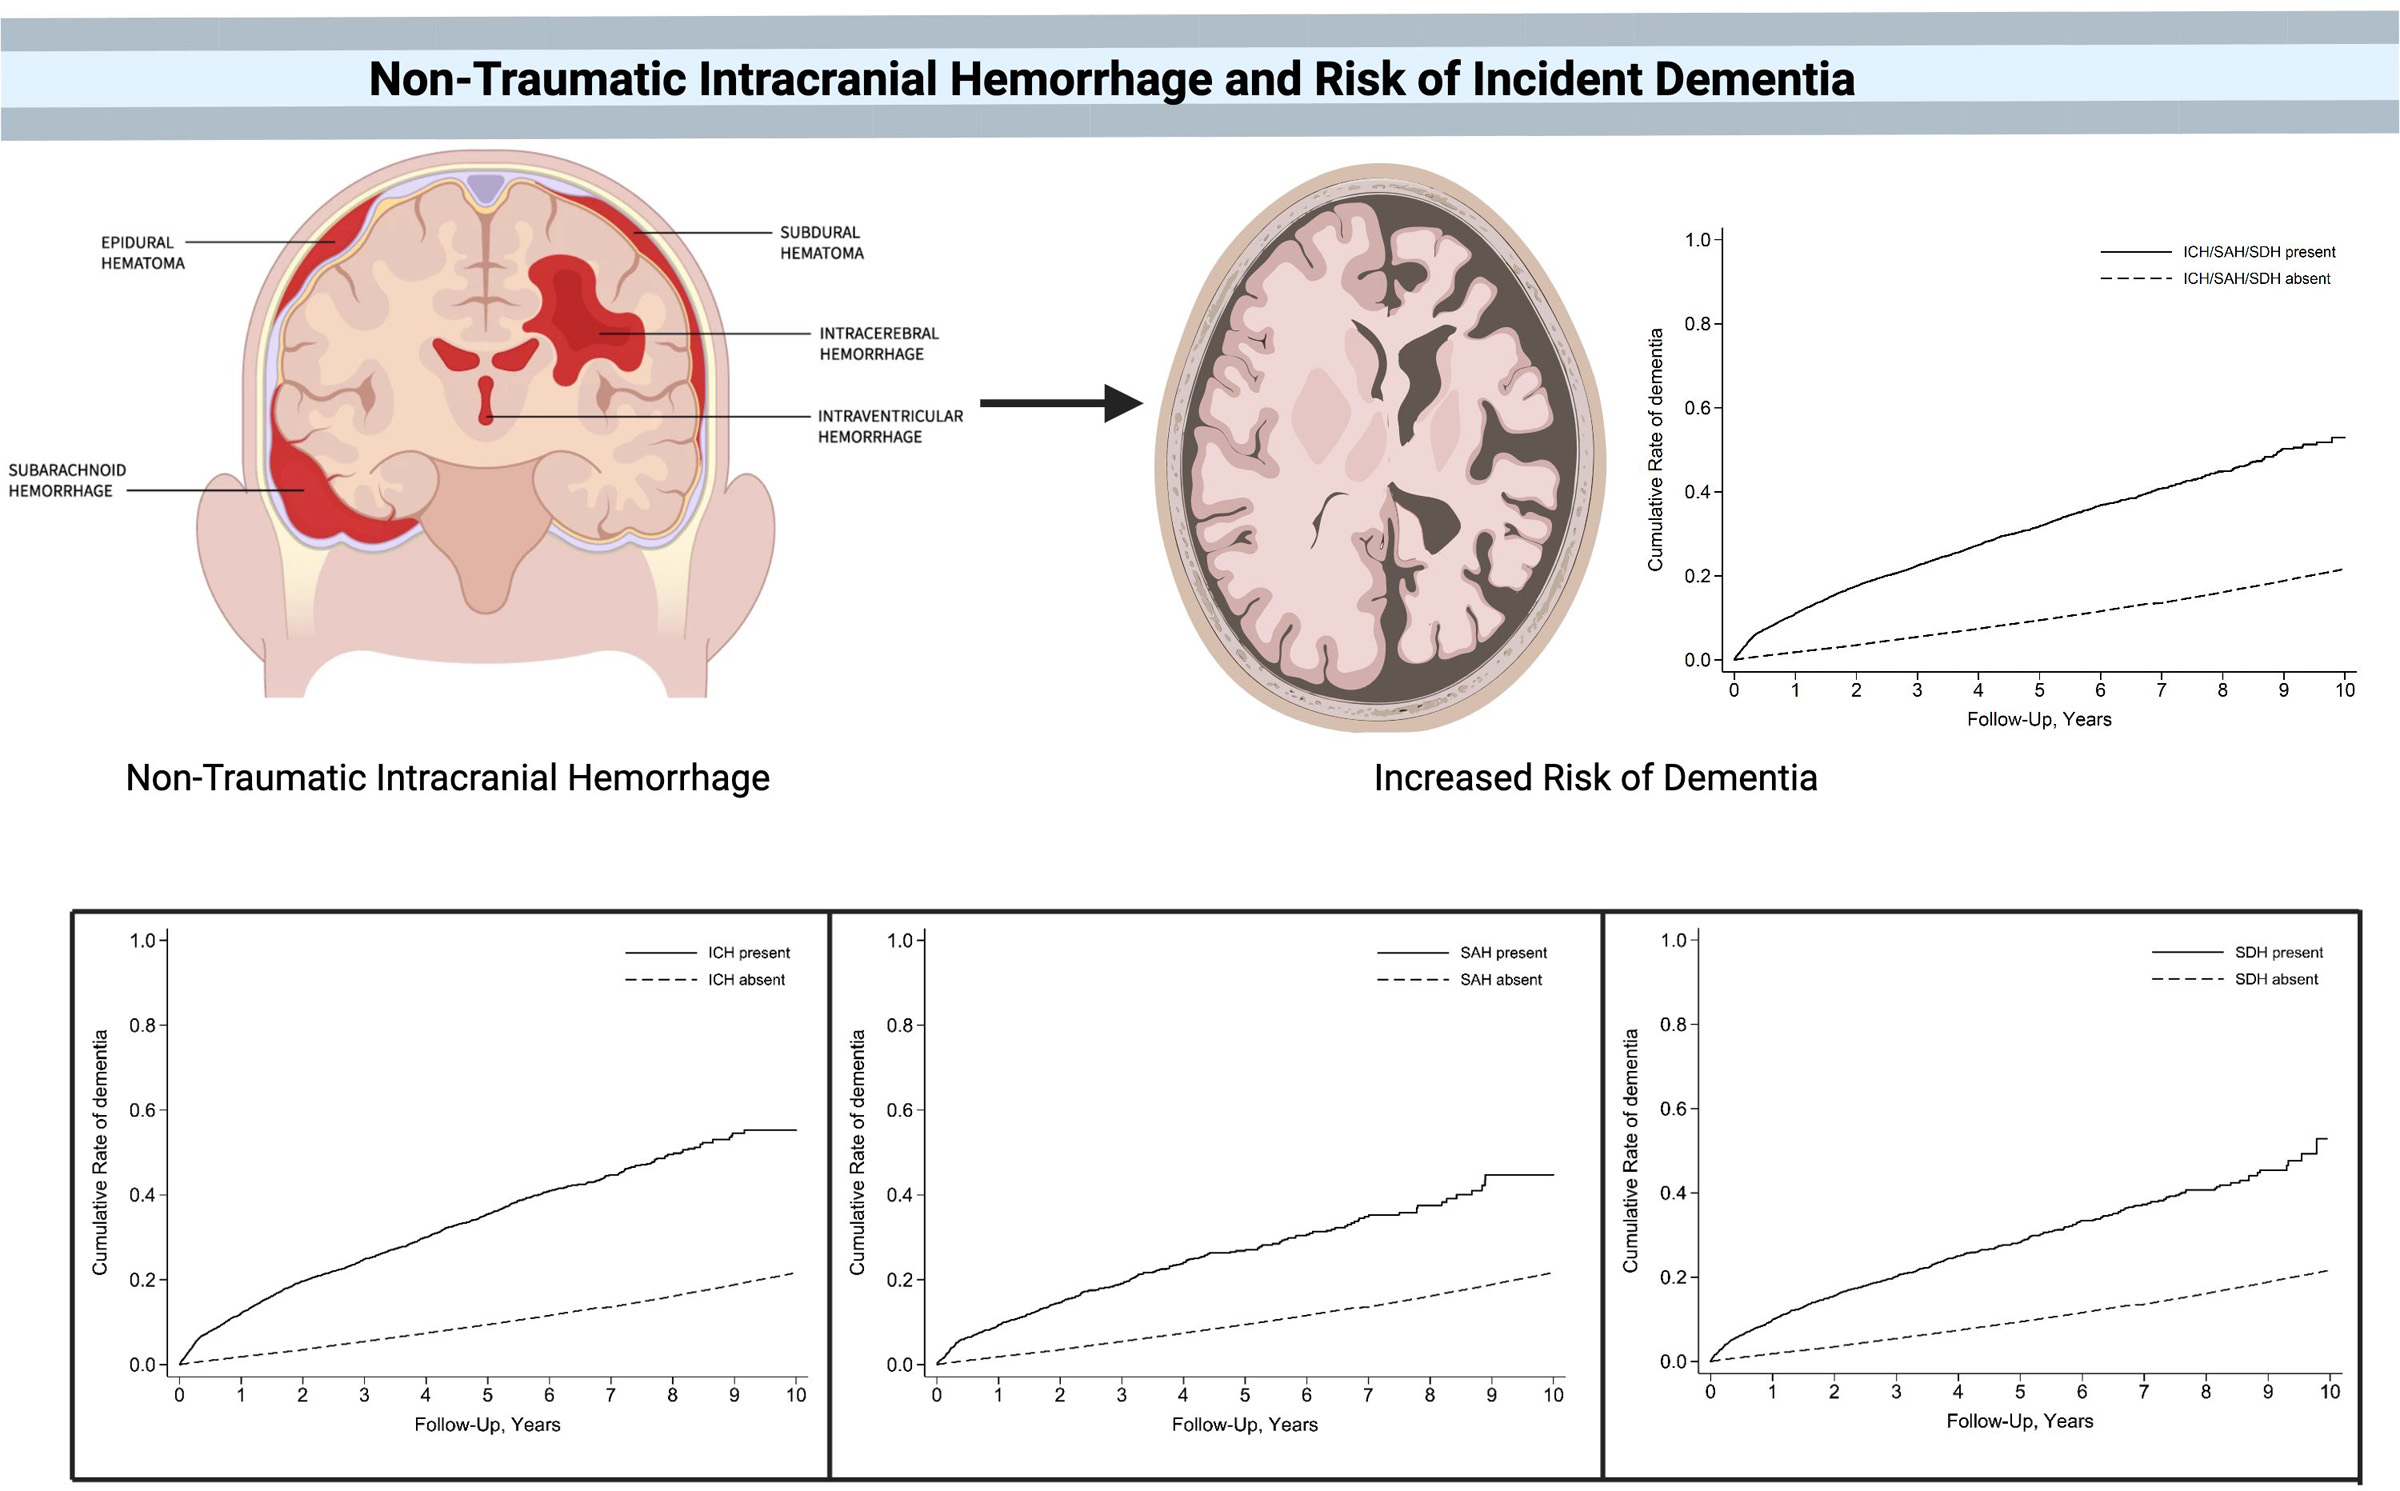

初売り 福袋 New Insights in Intracerebral Hemorrhage (Frontiers of 語学+参考書の詳細情報

New Insights in Intracerebral Hemorrhage (Frontiers of。Cerebral Hemorrhage: Pathophysiology, Treatment, and Future。Intracerebral Hemorrhage (Chapter 16) - Toole's。

NewInsightsinIntracerebralHemorrhage(FrontiersofNeurologyandNeuroscience)

SKargerAg

ToyodaKazunori

2015/11/17

3318055964

9783318055962

NewInsightsinIntracerebralHemorrhage(FrontiersofNeurologyandNeuroscience)

SKargerAg

ToyodaKazunori

2015/11/17

3318055964

9783318055962